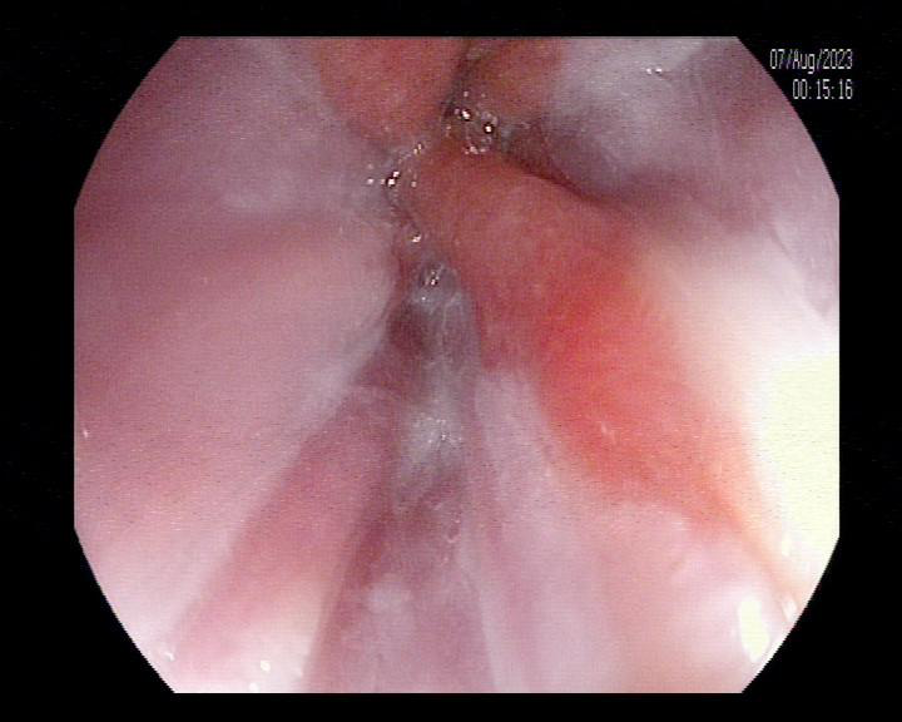

Nội soi đường tiêu hóa trên và làm sinh thiết tế bào giúp các Bác sĩ xác định được người bệnh có mắc Barrett thực quản hay không và mức độ tiến triển của bệnh thế nào để có những phương pháp điều trị hợp lý và chính xác. Phần lớn barret thực quản không có loạn sản, người bệnh nên nội soi định kì 6 – 12 tháng để theo dõi sự tiến triển của các tế bào trong thực quản.